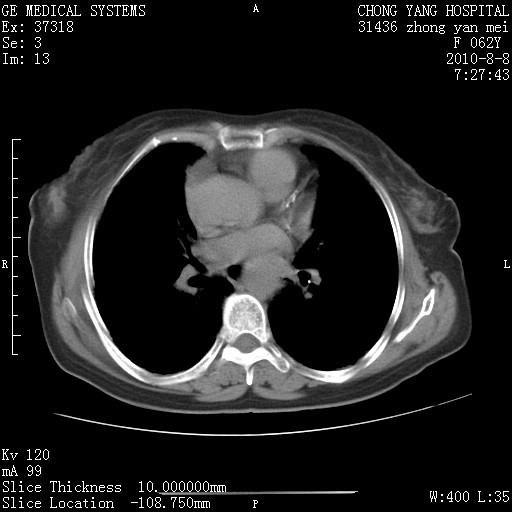

标题: CT28269:F62Y咳嗽胸痛数月。 [打印本页]

标题: CT28269:F62Y咳嗽胸痛数月。

1.肺间质纤维化.

2.纵隔淋巴结肿大。

3.迷走右锁骨下动脉。

两肺间质改变,纵隔淋巴结肿大,需要考虑结节病的可能。